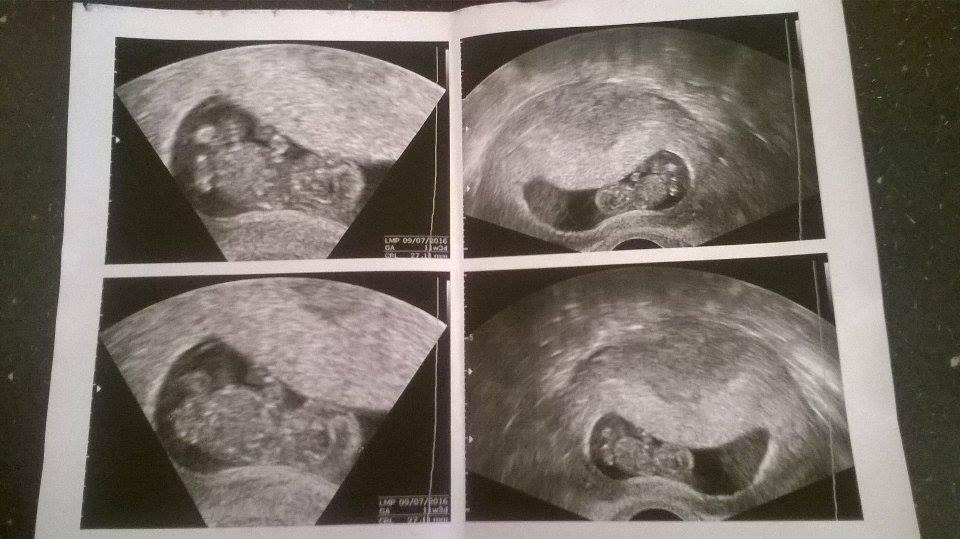

Já dobře, až teda na občasný zvracení, se cítím dobře. Ultrazvuk je z 27.9.